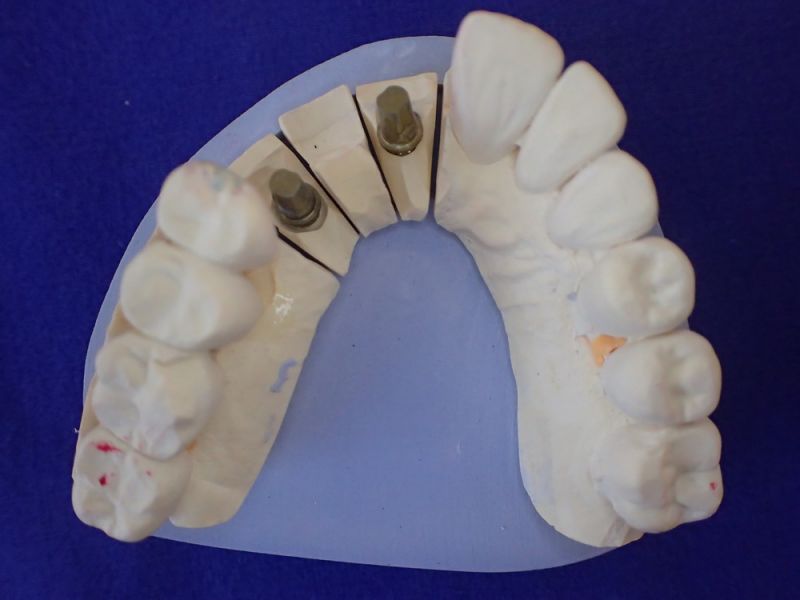

Kieler Patient erhält implantatgetragene Frontzahnbrücke

Was man an diesem Fall gut zu erkennen vermag, dass Patienten, die für sich irgendwann entschieden haben, nicht mit einem herausnehmbaren Zahnersatz ihren Lebensabend verbringen wollen auch nach und nach auf eine Implantatpfeilerstützzahl kommen, die genügend Substanz für die Lebensphase bieten, in der körpereigene Stützsubstanz, in Form von Zähnen zunehmend verloren geht.